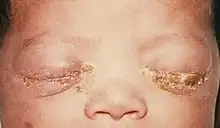

Le nouveau-né est parfois contaminé par la mère au moment de l'accouchement[33]. Plus tard l'enfant ou l'adolescent peut aussi être infecté en cas d'inceste, de viol ou de certains abus sexuel sur mineur[34] ou à l'occasion de jeux sexuels et de la découverte de la sexualité (en 1980, la moitié des cas de gonorrhée déclarés au Québec l'étaient chez des 15-19 ans).

Chez le nouveau-né

- Conjonctivite (prévenue par usage de collyre au nitrate d'argent en systématique)